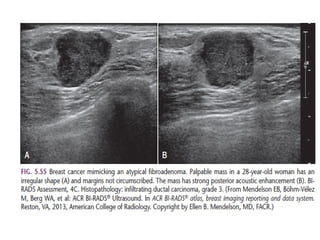

The shape of a mass is either round, oval or irregular.

Always make sure that a mass that is found on physical examination is

the same as the mass that is found with mammography or ultrasound.

The margin of a lesion can be:

Circumscribed (historically well-defined This is a benign finding.

Obscured or partially obscured, when the margin is hidden by superimposed

fibroglandular tissue. Ultrasound can be helpful to define the margin better.

Microlobulated. This implies a suspicious finding.

Indistinct (historically ill-defined).

This is also a suspicious finding.

Spiculated with radiating lines from the mass is a very suspicious finding.